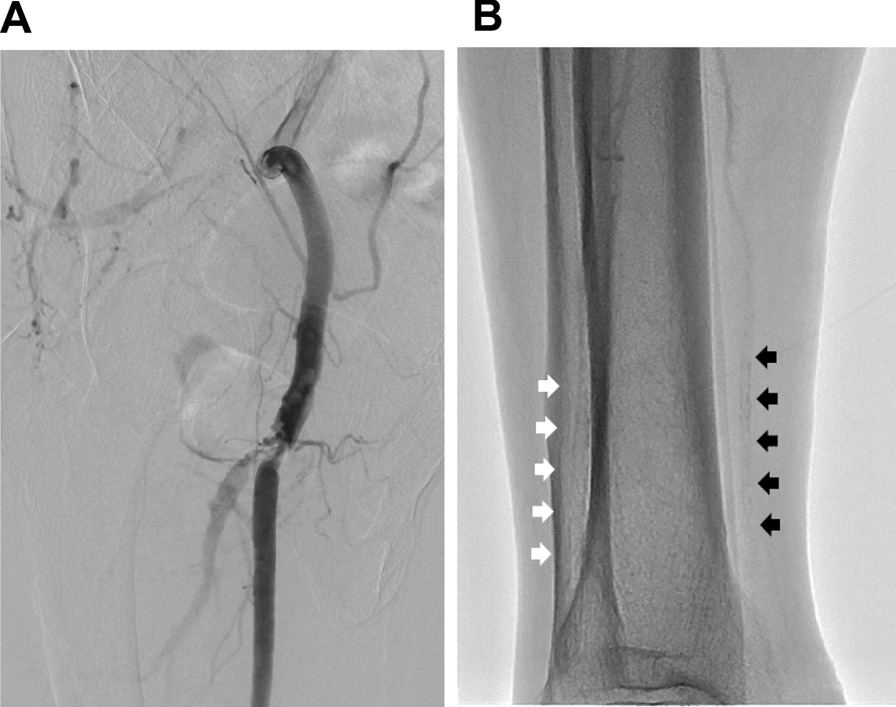

Fig. 2.

A Digital subtraction angiography in the right superficial femoral artery showing a severe stenotic lesion at the origin of the right superficial femoral artery. B Fluoroscopic image of the right lower leg showing severe calcification of the anterior tibial artery (white arrows) and posterior tibial artery (black arrows)